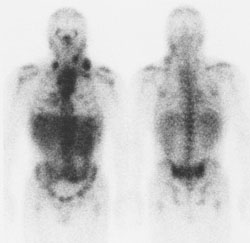

Nuclear Medicine: Page 409